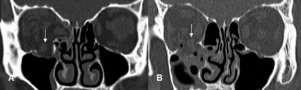

Introducción